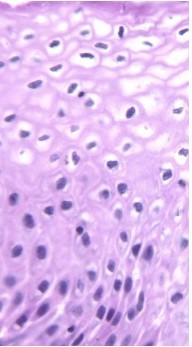

Here is a histologic sample of the cervix of a sexually active young woman. What is notable about the sample?

Cervical dysplasia:

Koilocytes from HPV infection: HPV has invaded basal cells. Crinkled, irregular nuclei with “normal maturation” of cells.